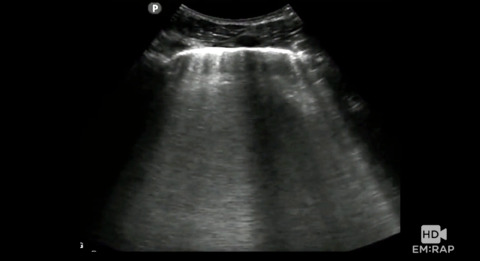

POCUS for Pulmonary Edema

How to do a Point of Care Ultrasound (POCUS) to assess for pulmonary edema. Presented by Dr. Jacob Avila, MD.